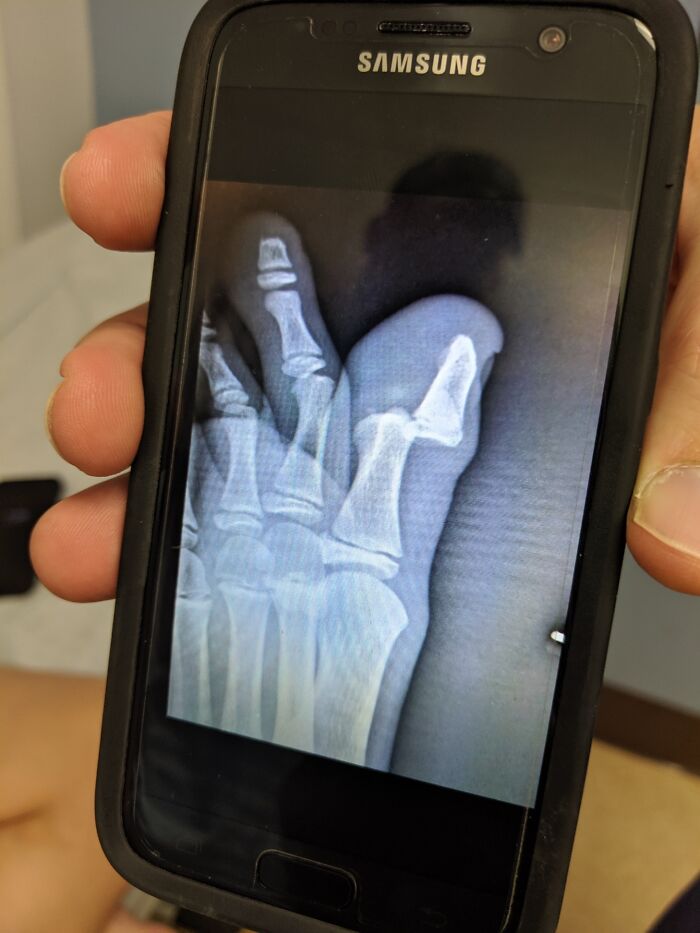

Mi hijo de 12 años se cayó de su bicicleta y se dislocó un dedo del pie